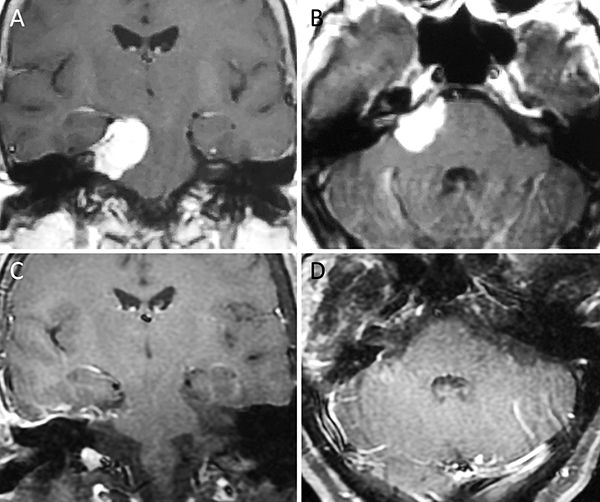

Figura 7. Meningioma de la convexidad lateral. A-B: RM preoperatoria; C-D: RM postoperatoria.